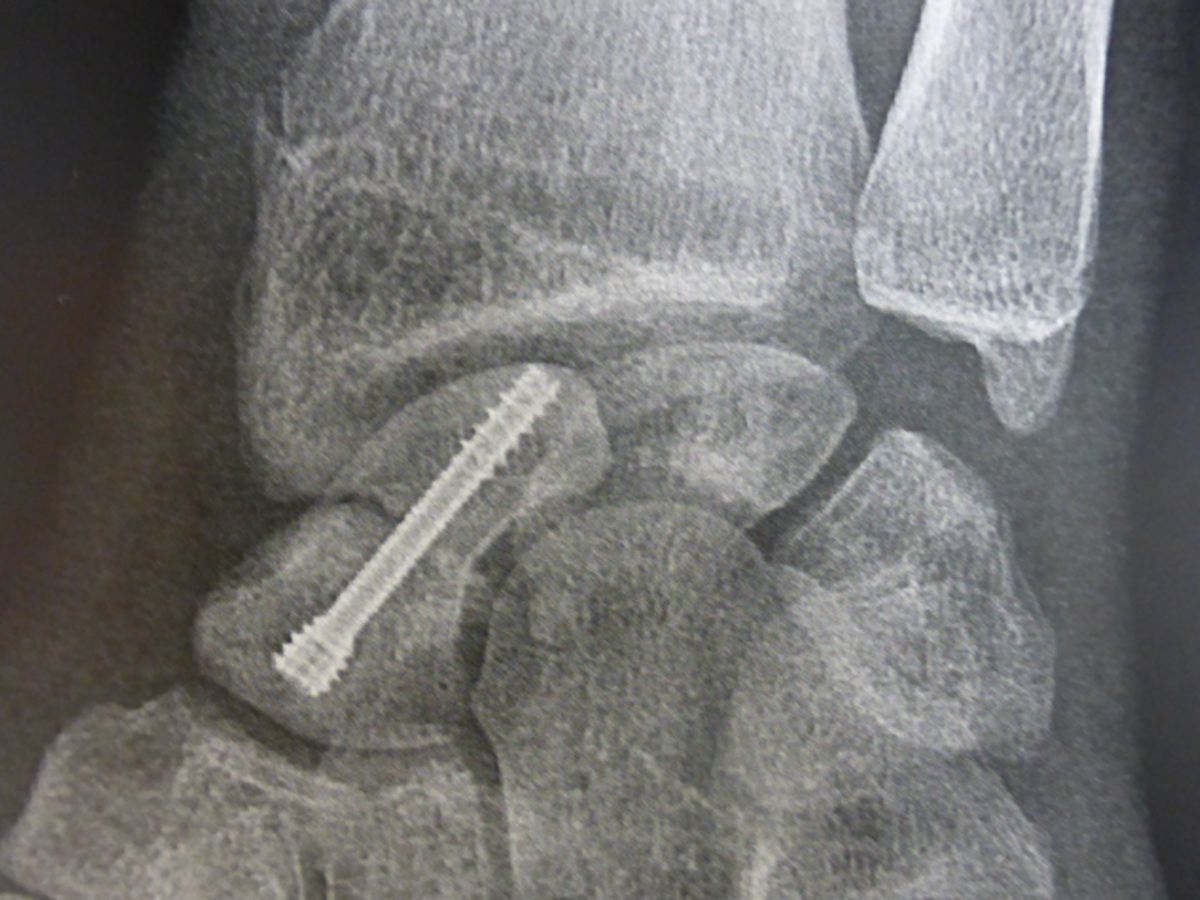

La vis est introduite à travers la peau par une très petite incision .

La vis est introduite par une toute petite incision. La position de la vis est contrôlée par des radiographies pendant l’intervention.

Une fois réduite, la fracture est toujours stabilisée par une vis ou des broches mise en place au bloc opératoire.

Ces fractures sont particulières car le pôle proximal du scaphoïde est la partie du scaphoïde qui consolide le plus difficilement. Il est maintenant admis que ces fractures doivent toujours être fixées chirurgicalement, même si elles ne sont pas déplacées. On utilise habituellement une ou deux vis.